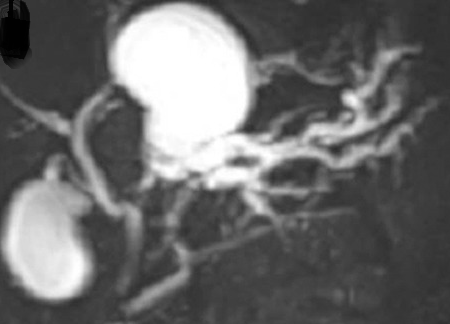

CT Angiography. Presence of a ruptured pseudoaneurysm of the common hepatic artery (Courtesy Dr. V. Penopoulos)